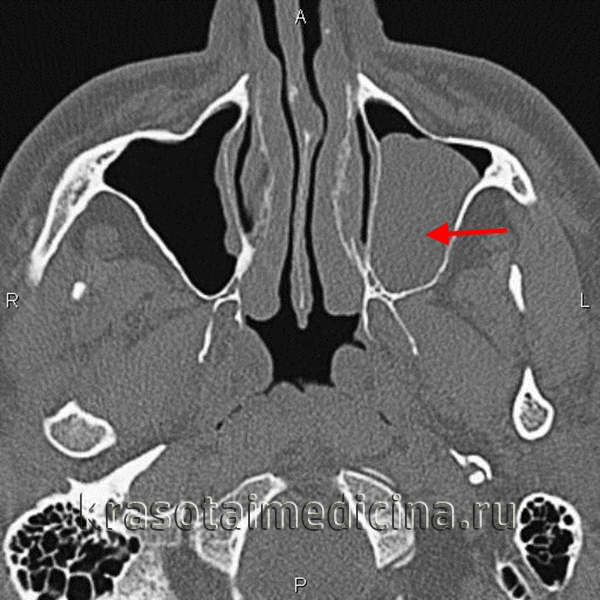

(Слева) На сагиттальной КЛКТ (реконструкций) визуализируется большое куполообразное объемное образование без кортикальной пластинки с плотностью мягких тканей (гиперденсное относительно воздуха), сопоставимое с муцинозной ретенционной псевдокистой верхнечелюстной пазухи. Край пазухи возле кисты интактен.

(Справа) На аксиальной КЛКТ (реконструкция) визуализируется муцинозная ретенционная псевдокиста, занимающая всю камеру правой верхнечелюстной пазухи на этом уровне. Важно не спутать перегородку в пазухе с кортикальной пластинкой на периферии образования. Обратите внимание на утолщение слизистой оболочки камер левой верхнечелюстной пазухи.

(Справа) На аксиальной КЛКТ (реконструкция) визуализируется муцинозная ретенционная псевдокиста, занимающая всю камеру правой верхнечелюстной пазухи на этом уровне. Важно не спутать перегородку в пазухе с кортикальной пластинкой на периферии образования. Обратите внимание на утолщение слизистой оболочки камер левой верхнечелюстной пазухи. (Слева) На периапикальной рентгенограмме задних отделов верхней челюсти справа, не содержащей зубов, на фоне воздуха визуализируется куполообразное затемнение в верхнечелюстной пазухе. Край пазухи возле затемнения интактен. Обратите внимание на наложение скулового отростка.

(Справа) На корональной КЛКТ (реконструкция) визуализируется куполообразная ретенционная псевдокиста в правой верхнечелюстной пазухе. Кортикальная пластинка на периферии псведокисты отсутствует, края пазухи интактны.